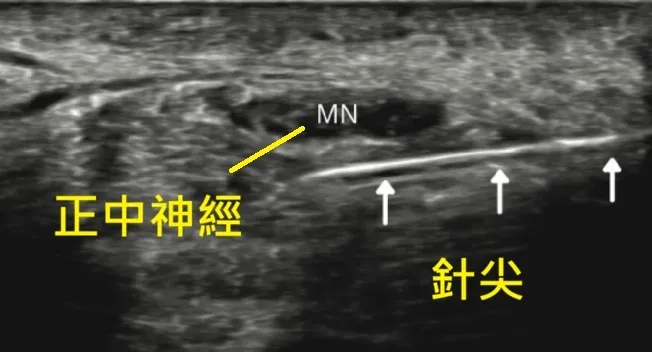

2. 黃金治療:超音波導引神經解套注射

這是宸新復健科的專長項目。我們使用高解析超音波,清楚看到被壓扁的正中神經。接著利用長針,將藥水(低濃度葡萄糖或 PRP)精準注入神經與橫腕韌帶之間。

原理: 利用液體的壓力,將沾黏的組織「剝離/撐開」 (Hydrodissection),瞬間解除神經的壓迫,並提供神經修復所需的養分。就像幫神經開了一條新的高速公路,患者常感覺「手鬆開了」。